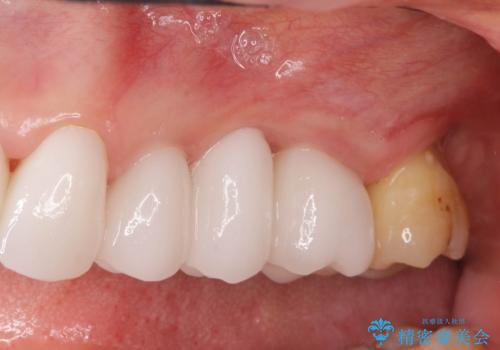

- 39.6万円(ジルコニアクラウン×3・仮歯×3)費用は治療当時の料金となります

治療前よりも高い位置で歯ぐきが保たれ、清掃性の高いブリッジ治療を行うことができました。